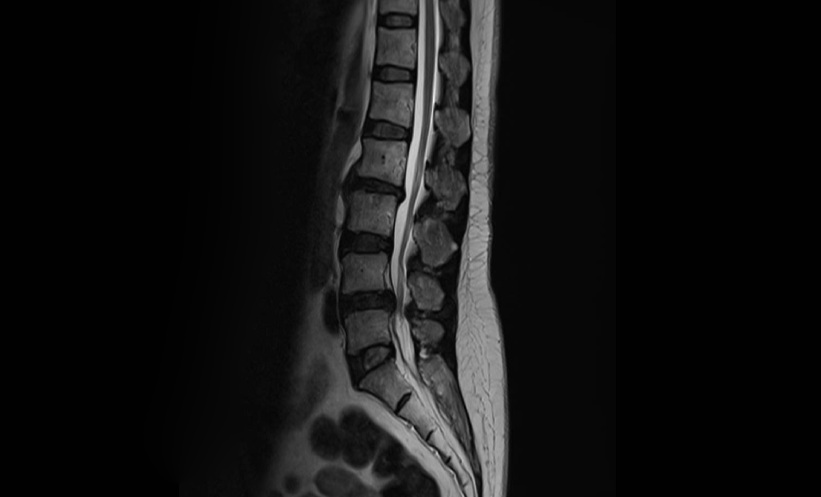

Understanding Becker Muscular Dystrophy: Disease Overview & Natural History

This infographic presents an overview of Becker Muscular Dystrophy outlining the disease itself, exploring the diagnosis of the disease and discusses tracking the natural history of Becker.